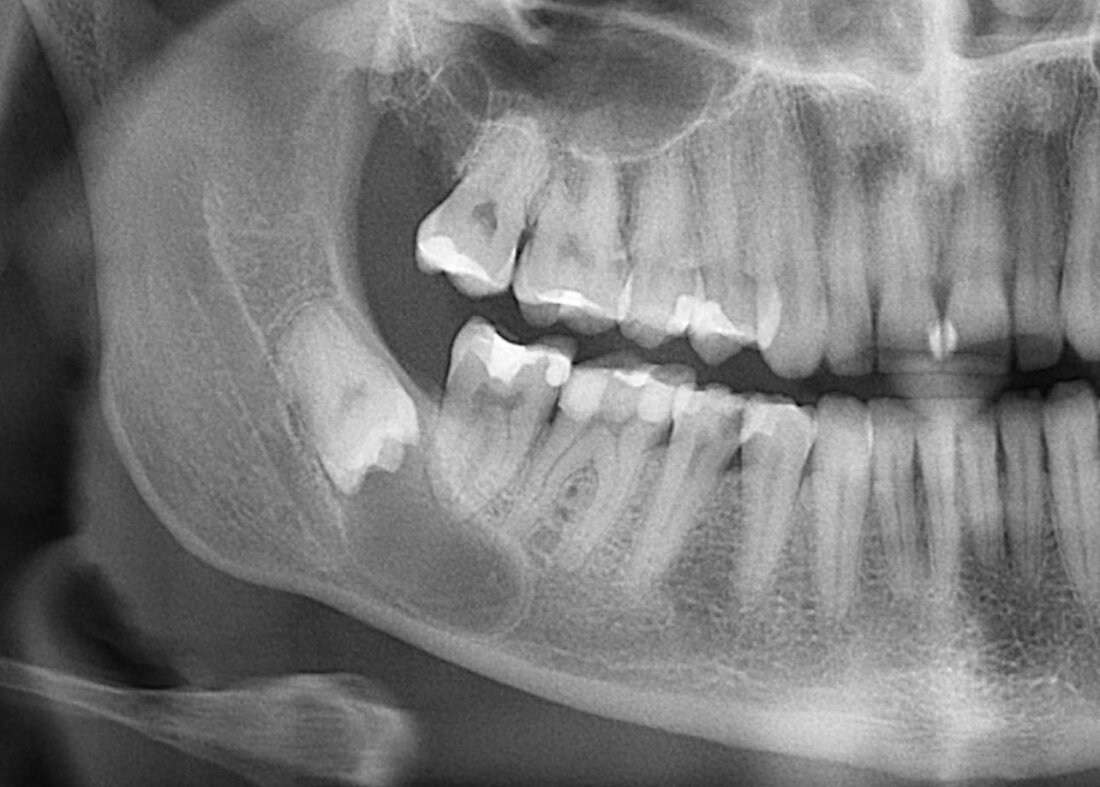

1. Зубы мудрости.

Раньше эти "бандиты", бесцеременно появляющиеся в рядах зубов и доставляющие достаточно хлопот почти каждому их обладателю, раньше имели немалое значение, когда рацион наших предков состоял, в основном, из твердой и жесткой пищи. Но со временем люди сообразили готовить пищу на огне, поэтому жевать надо было меньше без использования силы, с которой можно перекусить канат. Помимо этого люди думали и придумывали все больше, что заставляло их мозг расти, а челюсть уменьшаться.